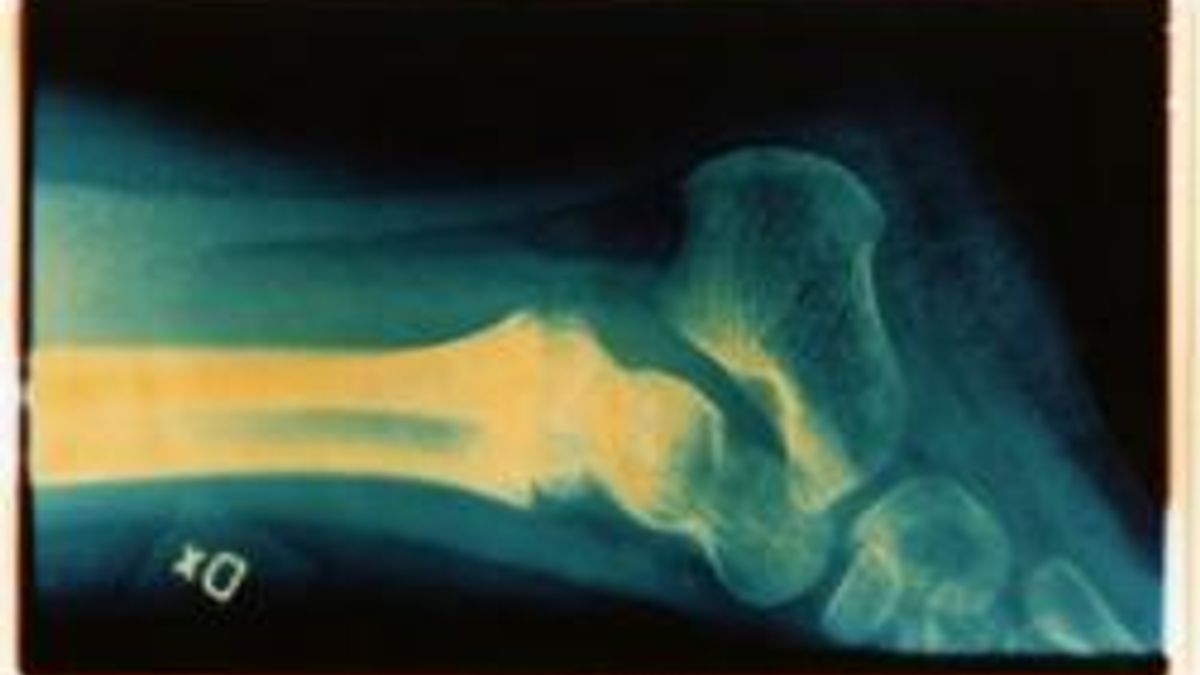

Gli esperti: "Osteoporosi maschile trascurata"

L'osteoporosi è principalmente un problema femminile, visto che colpisce nell'80 per cento dei casi le donne, ma non bisogna dimenticare che ne soffrono anche gli uomini che la trascurano di più. Se ne discute a Roma nel congresso internazionale Gender and Science al Policlinico Umberto I. Il convegno è organizzato dall'Università Sapienza di Roma con l'Università di Sassari ed è promosso dalla Fondazione internazionale Menarini.